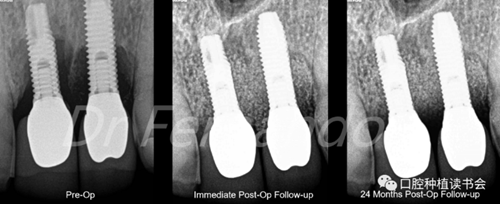

有的學(xué)者建議,作為診斷標準,在探診深度≥4 mm伴出血的情況下,種植體黏膜炎可以通過機械清創(chuàng)和洗必泰化學(xué)治療的保守治療方案治愈(1, 2) 。種植體周圍炎除涉及黏膜外,還涉及種植體周圍的骨組織。X光片診斷種植體周圍存在骨喪失,并伴有探診深度≥為5 mm和探診出血(圖2)

圖2 前牙美學(xué)區(qū)種植體周圍炎,出現(xiàn)明顯的骨喪失

盡管手術(shù)治療似乎能改善結(jié)果;但只有將手術(shù)治療和骨再生相結(jié)合才能獲得更高的成功率。Schwarz等人發(fā)現(xiàn)這種再生手術(shù)治療有2年以上的滿意效果,能使種植體周圍的骨吸收停止,探診出血率由80%降至34%(圖5 )。

圖5通過手術(shù)治療,種植體周圍獲得骨再生,術(shù)后2年效果穩(wěn)定(圖2、圖4相同病例)